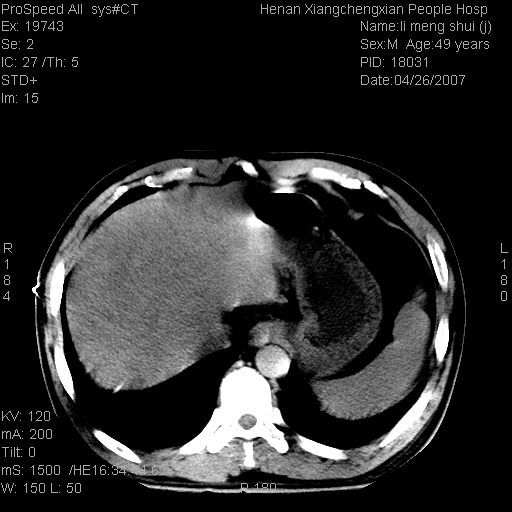

| 患者,男,49岁, 腹疼伴恶心\\呕吐20天,20天前无明显诱因出现右上腹部疼痛,钝疼,无放射,伴恶心\\呕吐,不伴发热.患者不愿增强. b超:肝脏右叶实性占位. ct:肝脏右叶可见一巨块状圆形低密度影,大小约93mm*84mm,其内可见点状高密度影,胆囊、胰腺、脾脏大小、形态及密度未见异常,腹膜后间隙未见肿大淋巴结影。 印象:肝脏右叶巨大肿块,性质待定,建议增强并穿刺活检进一步确诊。 ct平扫: ![]() ![]() ![]() ![]() ![]() ![]() ![]() ![]() ![]() ![]() ![]() ![]() ![]() ![]() ![]() ![]() ![]() 肝脏右叶肿块ct引导下穿刺活检术 患者于16时05分仰卧于ct检查台上,首先行肝脏ct扫描确定进针位置、深度、角度。在局麻下行ct引导下肝脏右叶肿块穿刺活检术。常规消毒、铺巾、局麻。在ct引导下使活检针经右侧腋中线、第9肋间隙垂直胸壁进针90mm,针头进入病变预定位置。在病变预定位置多点、多方向抽取小米样病变组织多块,涂片五张送病理检查。术后穿刺点局部无出血,未出现腹腔积液等并发症。术中及术后患者生命体征稳定,手术于17时10分成功完成。患者安返病房。 穿刺片 ![]() ![]() ![]() ![]() ![]() ![]() ![]() ![]() ![]() ![]() ![]() ![]() ![]() ![]() ![]() ![]() 病理结果肝细胞癌 ![]() 原贴地址:http://www.radinet.com.cn/forum_view.asp?forum_id=4&view_id=24130 ok |